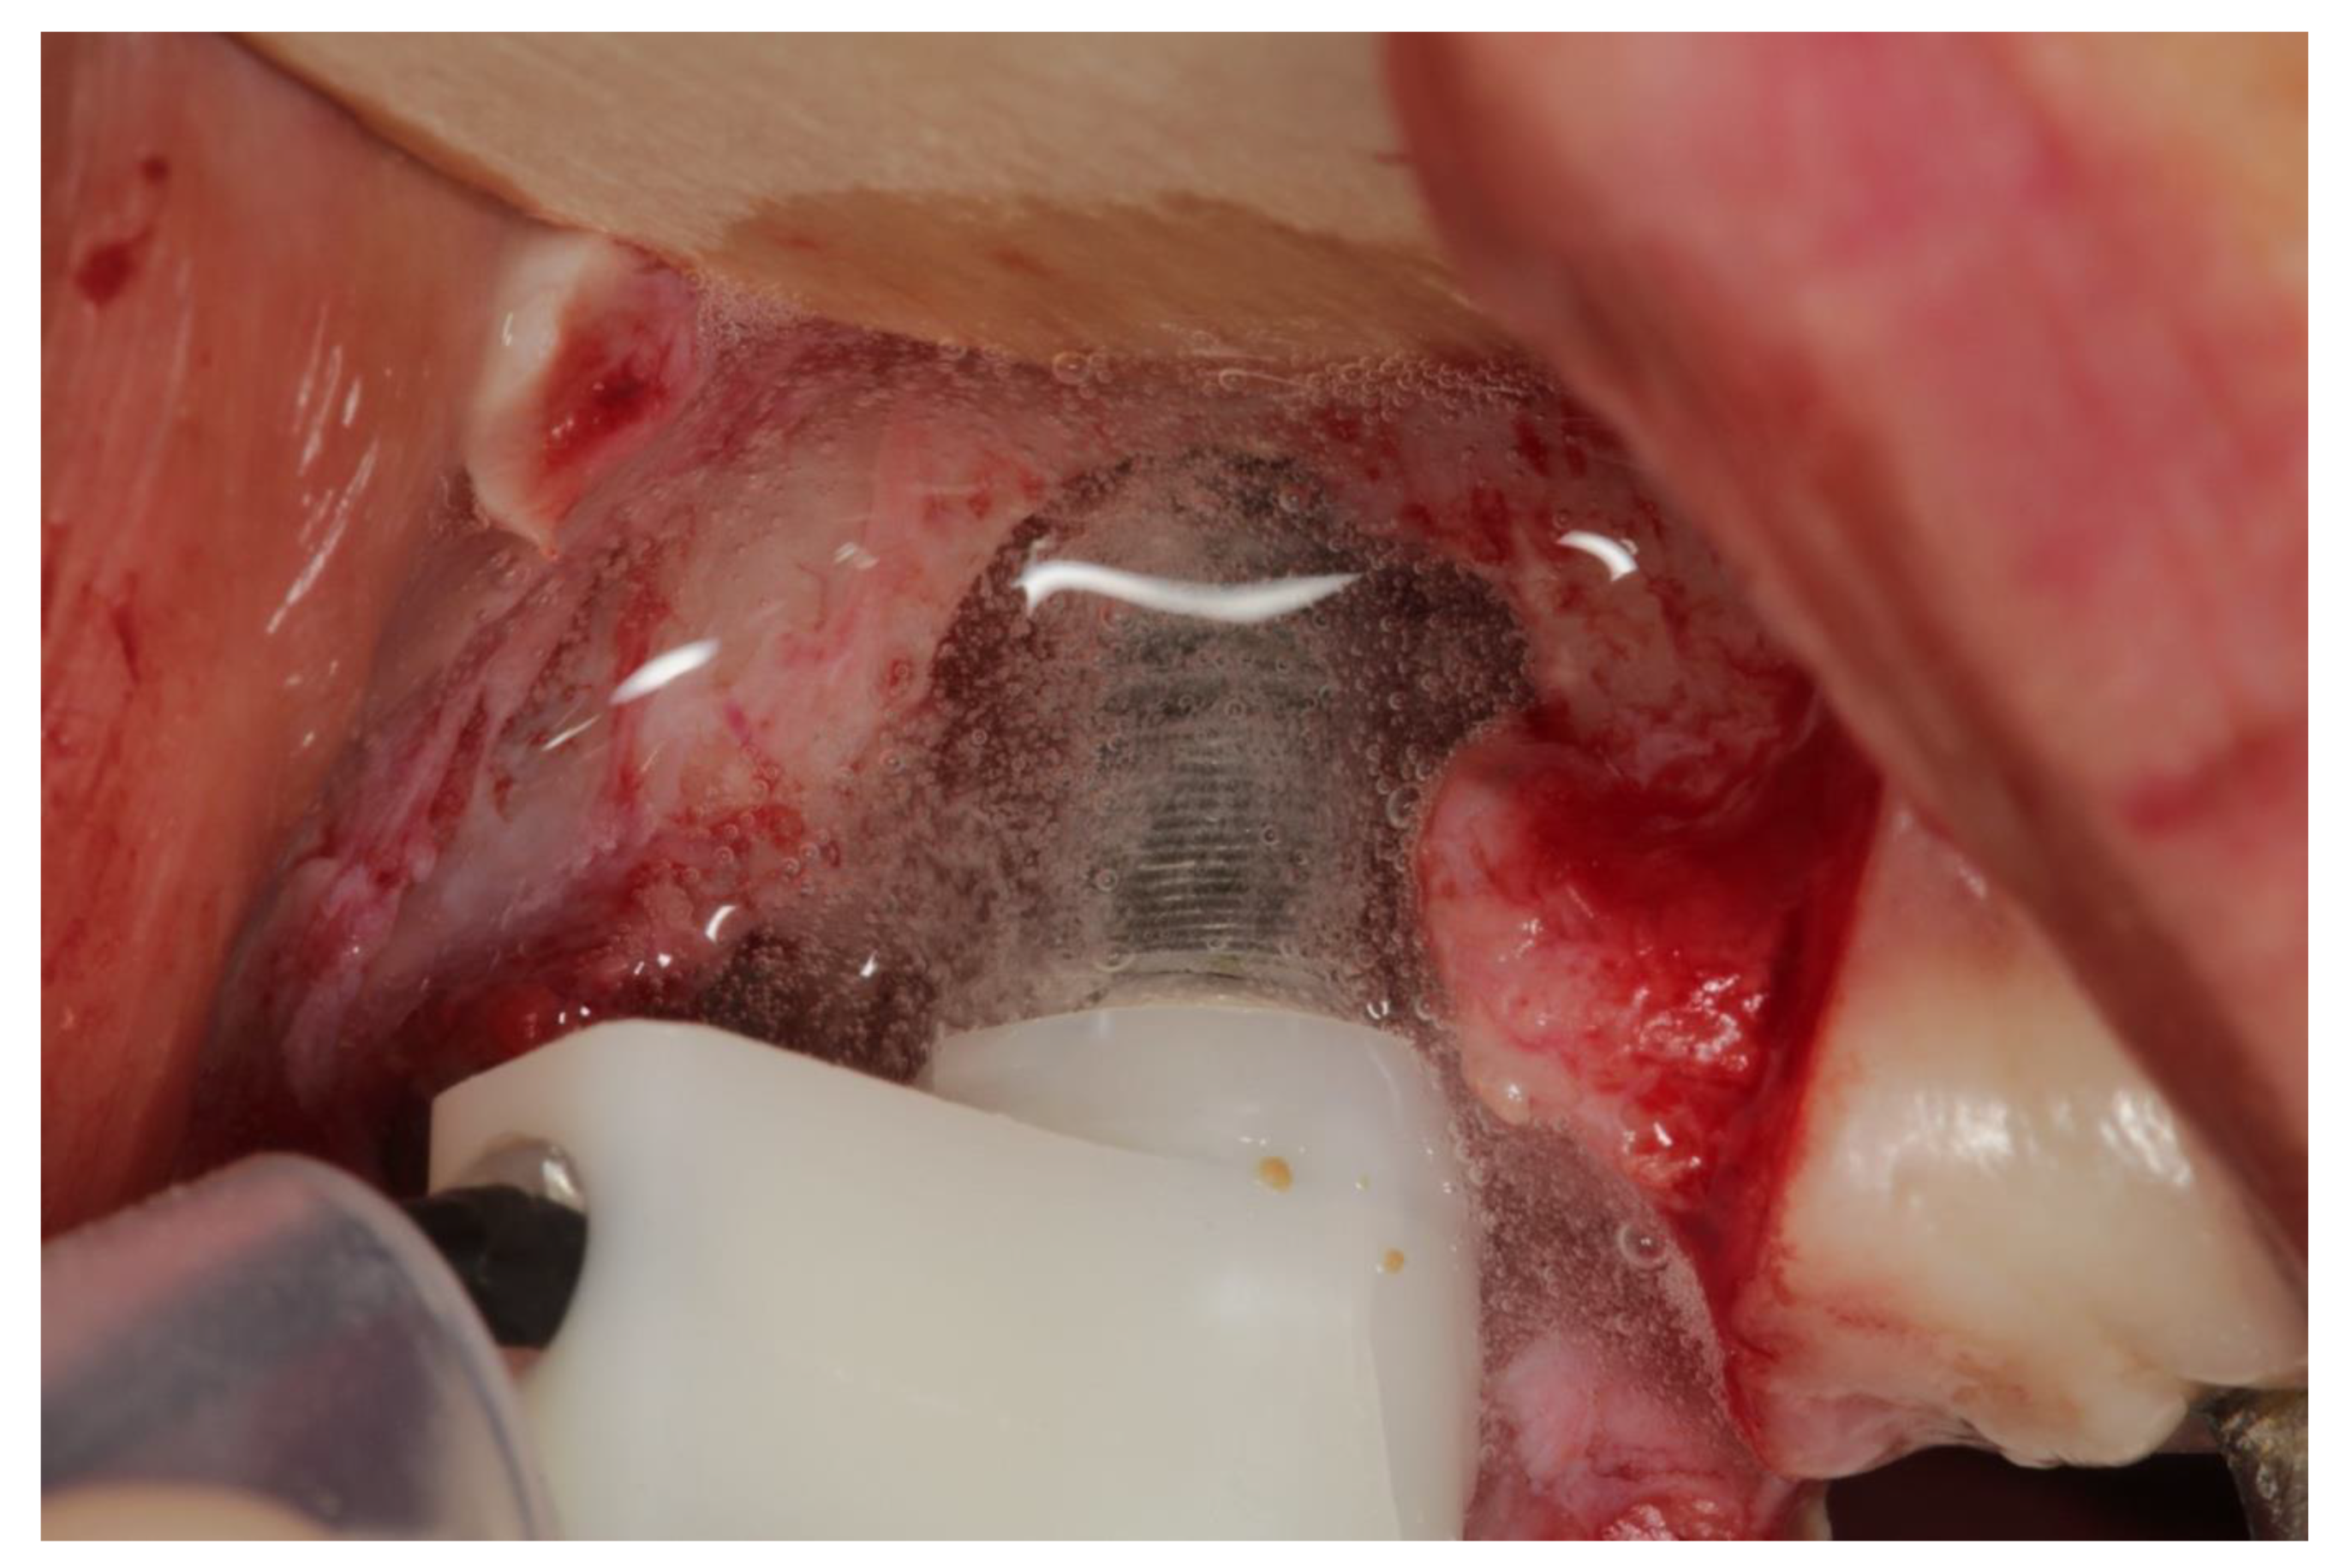

2.3. Devices and Mode of Action